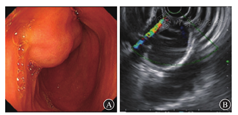

实验室检查:血常规示白细胞计数为3.82×109/L,中性粒细胞占比为0.358,红细胞计数为4.51×1012/L,血红蛋白为118 g/L,血清肿瘤标志物、血生物化学指标、ESR、尿粪常规检查均未见异常。电子胃镜检查示十二指肠降部黏膜下隆起(图1A)。超声胃镜提示十二指肠降部固有肌层低回声病灶(图1B)。上腹部CT增强检查示十二指肠水平部与升部交界处类圆形低密度影,考虑肠重复畸形或肠壁来源囊性良性病变可能性大(图2A)。上消化道钡剂造影检查提示十二指肠降部与水平部交界处外压性充盈缺损,可随肠管蠕动,考虑重复畸形可能性大(图2B)。